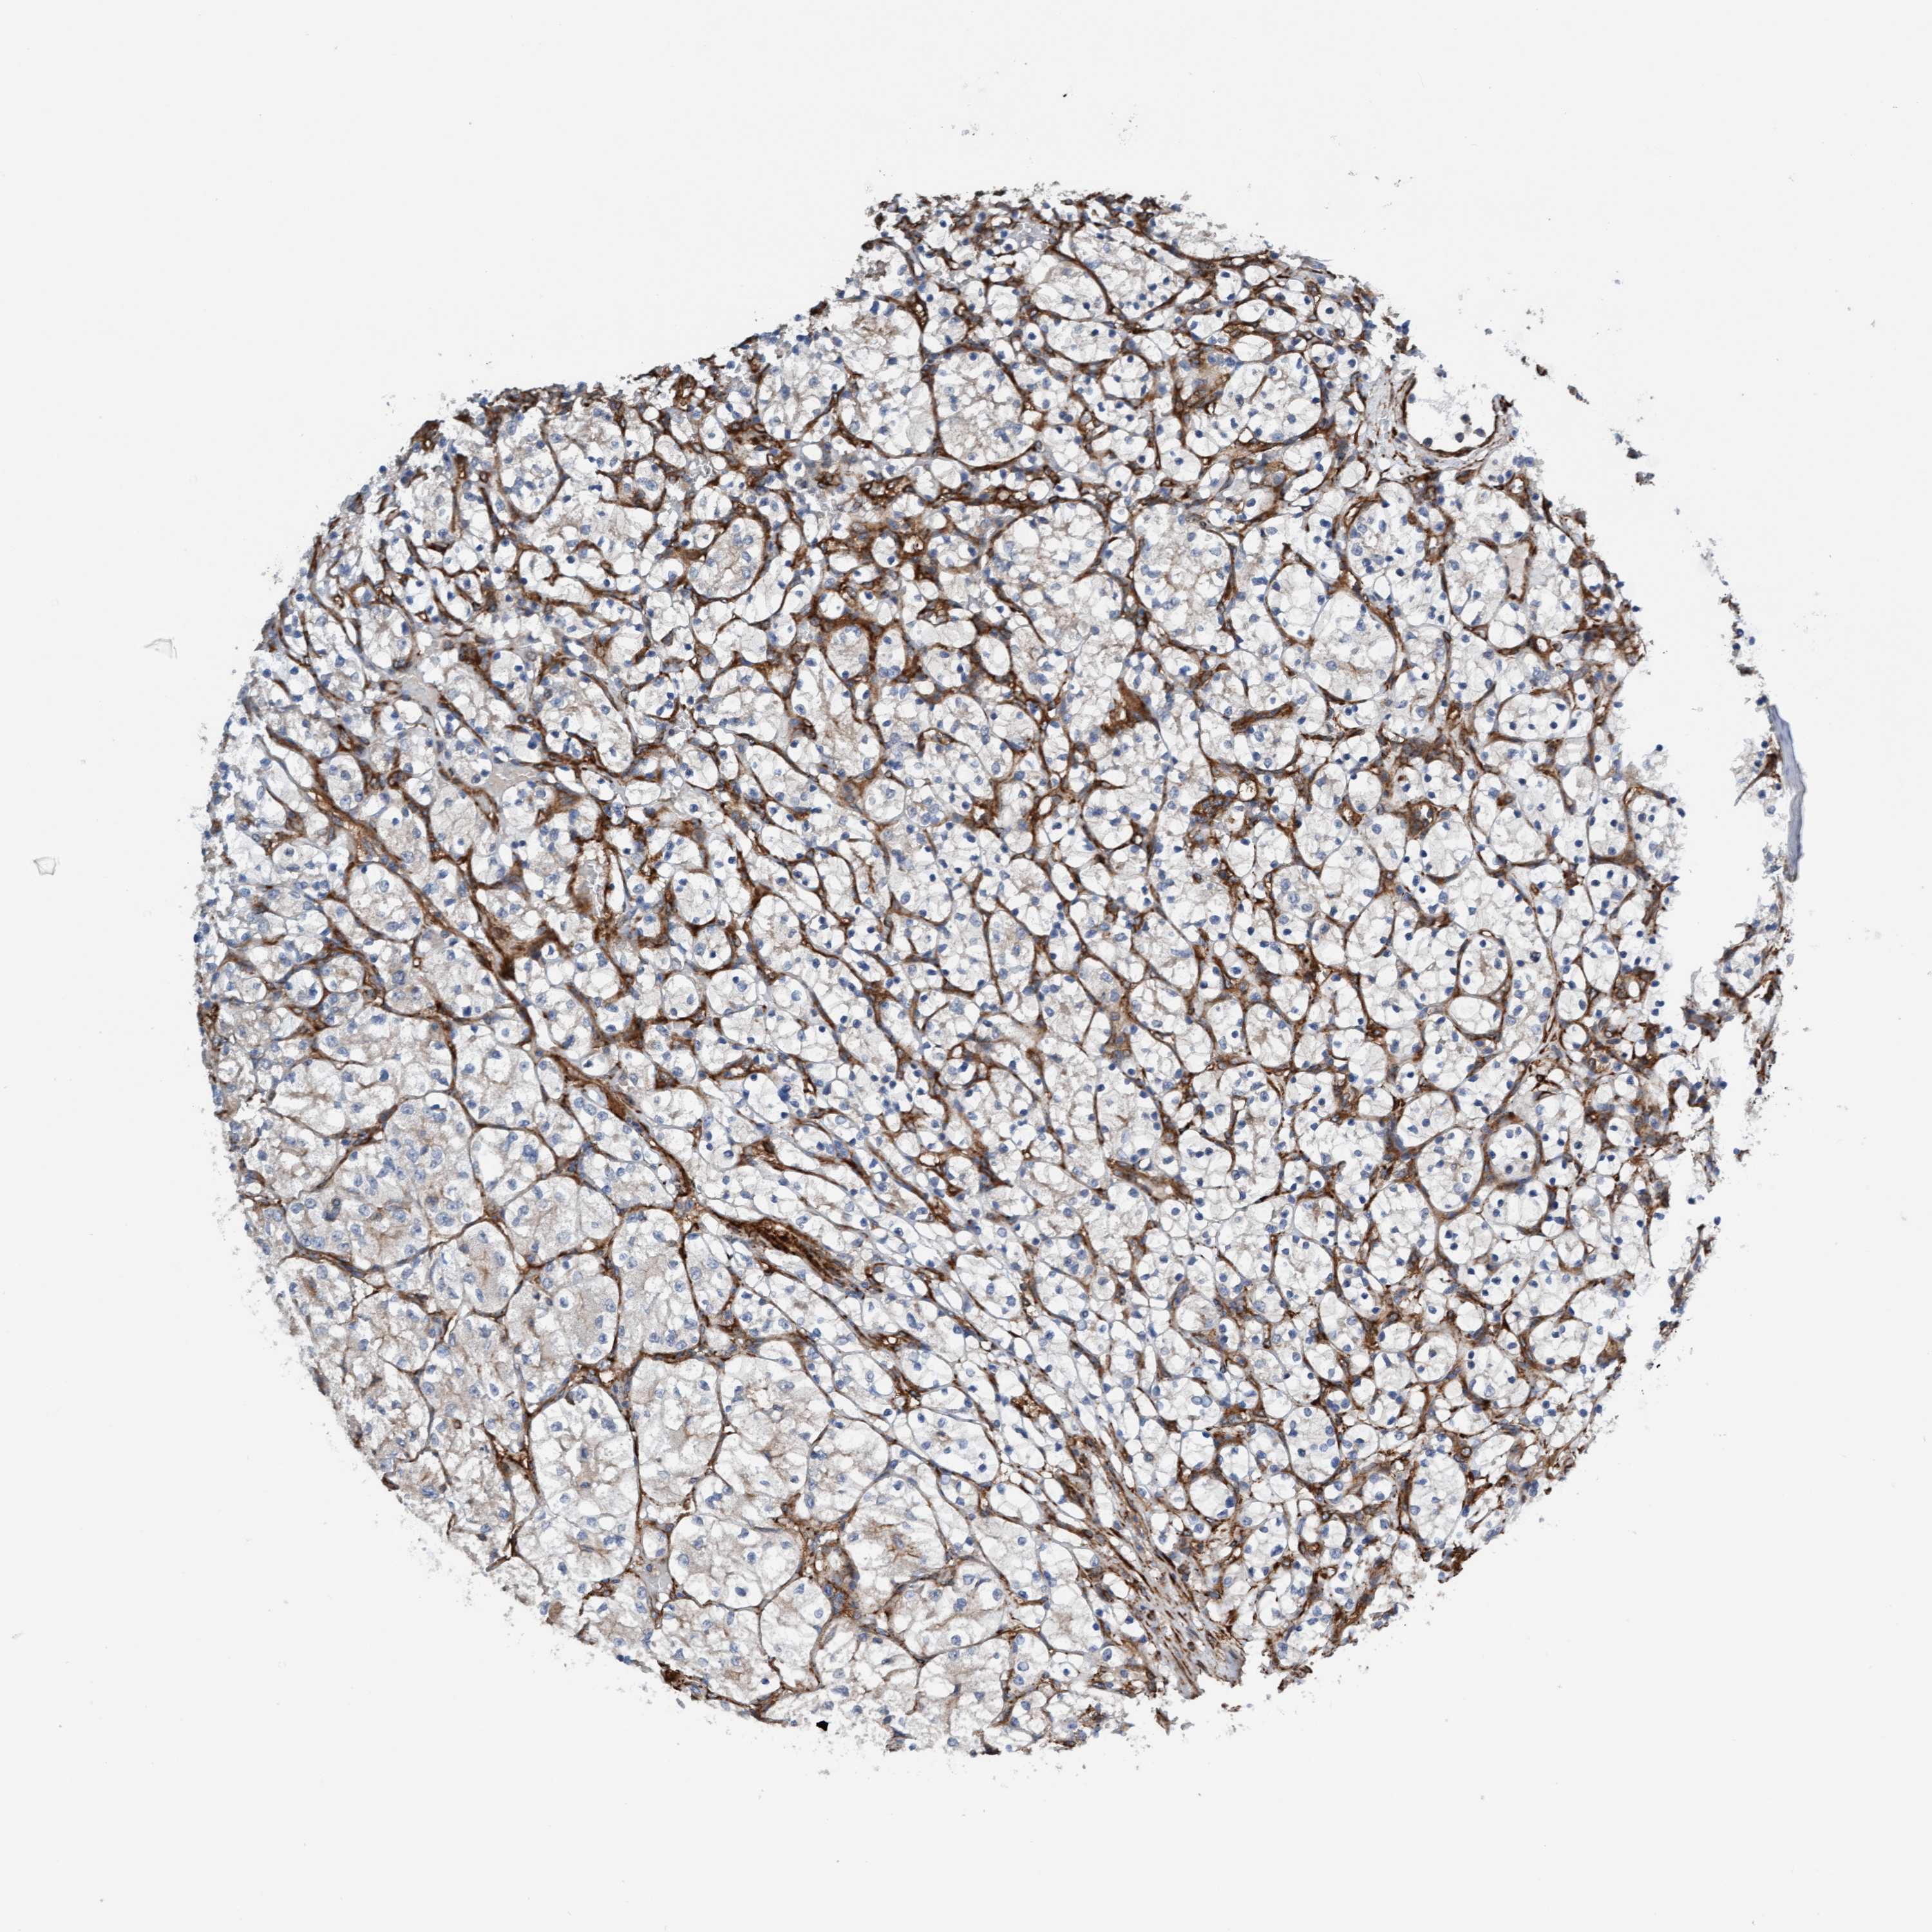

KIDNEY RENAL CLEAR CELL CARCINOMA (VALIDATION) - Interactive survival scatter ploti

The Survival Scatter plot shows the clinical status (i.e. dead or alive) for all individuals in the patient cohort, based on the same data that underlies the corresponding Kaplan-Meier plots. Patients that are alive at last time for follow-up are shown in blue and patients who have died during the study are shown in red.

The x-axis shows the expression levels (FPKM) of the investigated gene in the tumor tissue at the time of diagnosis. The y-axis shows the follow-up time after diagnosis (years). Both axes are complimented with kernel density curves demonstrating the data density over the axes. The top density plot shows the expression levels (FPKM) distribution among dead (red) and alive patients (blue). The right density plot shows the data density of the survived years of dead patients with high and low expression levels respectively, stratified using the cutoff indicated by the vertical dashed line through the Survival Scatter plot. This cutoff is automatically defined based on the FPKM cutoff that minimizes the p-score. The cutoff can be changed by dragging the vertical line or by entering a cutoff value in the square labeled "Current cut-off".

Under the Survival Scatter plot the p-score landscape (black curve; left axis) is shown together with dead median separation (red curve; right axis). Dead median separation is the difference in median mRNA expression between patients who have died with high and low expression, respectively. It is calculated as follows: median FPKM expression of dead patients with high expression - median FPKM expression of dead patients with low expression. This is intended to aid the user in visually exploring custom cutoffs and the associated p-scores and dead median separation.

Individual patient data is displayed and can be filtered by clicking on one or more of the category buttons on the top of the page. Categories describing expression level and patient information include: high, low, alive, dead, female, male and tumor stages. The scale of the x-axis can be toggled between linear and log-scale by clicking on the "x log" button. Mouse-over function shows TCGA ID, patient information and mRNA expression (FPKM) for each patient.

& Survival analysisi

Kaplan-Meier plots summarize results from analysis of correlation between mRNA expression level and patient survival. Patients were divided based on level of expression into one of the two groups "low" (under cut off) or "high" (over cut off). X-axis shows time for survival (years) and y-axis shows the probability of survival, where 1.0 corresponds to 100 percent.

FMNL3 is validated prognostic, high expression is favorable in Kidney Renal Clear Cell Carcinoma (validation)

Best expression cut offi

Based on the FPKM value of each gene, patients were classified into two groups and association between prognosis (survival) and gene expression (FPKM) was examined. The best expression cut-off refers the FPKM value that yields maximal difference with regard to survival between the two groups at the lowest log-rank P-value. Best expression cut-off was selected based on survival analysis .

When clicking on this number, the vertical dashed line indicating cut-off, the interactive survival plot, and the Kaplan-Meier curve will be adjusted to show results based on the best expression cut-off.

: 27.36

P scorei

Log-rank P value for Kaplan-Meier plot showing results from analysis of correlation between mRNA expression level and patient survival.

N/A

5-year survival highi

5-year survival for patients with higher expression than the expression cutoff.

For melanoma and glioma, 3-year survival is shown.

5-year survival lowi

5-year survival for patients with lower expression than the expression cutoff.

TCGA RNA samplesi

RNA-seq data is reported as average FPKM (number Fragments Per Kilobase of exon per Million reads), generated by the The Cancer Genome Atlas (TCGA) .

Normal distribution across the dataset is visualized with box plots, shown as median and 25th and 75th percentiles. Points are displayed as outliers if they are above or below 1.5 times the interquartile range. FPKM values of the individual samples are presented next to the box plot.

Average pTPM 23.2

Number of samples 100